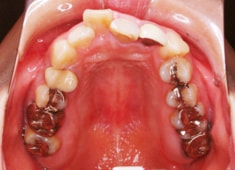

治療前